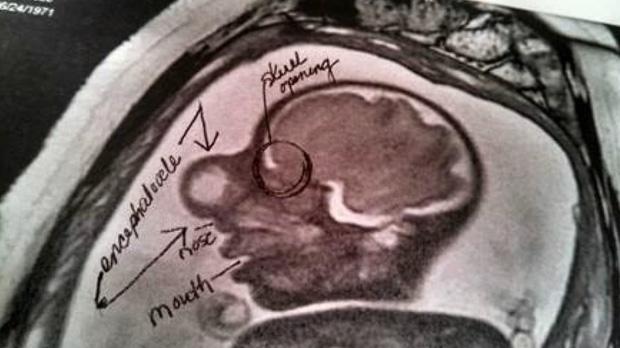

Hình ảnh chụp MRI khi Zakary còn ở trong bụng mẹ

Hộp sọ của em bé không đóng lại đúng cách khi phát triển, khiến một số mô não dần vươn ra ngoài, qua khoảng trống bên trong phần xương giữa hai mắt và tụ lại trong một cái túi. Trung tâm Kiểm soát và Phòng ngừa Dịch bệnh ước tính chỉ có một trên 12.200 trẻ sinh ra ở Hoa Kỳ mắc dị tật tương tự Zakary, đồng nghĩa, trường hợp của bé là vô cùng hiếm gặp.